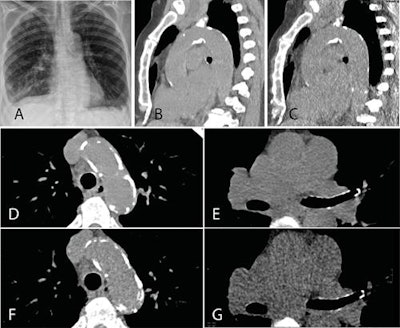

A: Representative posteroanterior chest x-ray image. B, D, and E: Transverse CT sections scanned with standard-dose CT (effective dose 1.57 mSv). C, F, and G: Ultralow-dose CT (effective dose 0.12 mSv) in an 83-year-old woman with a body mass index of 26.1 kg m2. As the images illustrate, ultralow-dose CT allows for anatomically differentiated assessment, with a high agreement of calcium quantity estimation of the aortic valve, ascending aorta, and aortic arch as compared with standard-dose CT. Image courtesy of BJR and Dr. Michael Messerli et al.Their study included a total of 106 patients, 43 (41%) women and 63 (59%) men, from a prospective single-center study. In the same session, these patients underwent standard-dose chest CT with 110 kV (1.7 ± 0.7 mSv) by clinical indication followed by ultralow-dose CT with 100 kV and spectral shaping by a tin filter (0.13 ± 0.01 mSv) to achieve an equivalent dose to chest. All scans were conducted on a third-generation dual-source CT scanner (Somatom Force, Siemens Healthineers).

Two independent radiologists reviewed the images, rated image quality, and estimated the presence and extent of calcification of the aortic valve, ascending aorta, and aortic arch. X-rays also were included if they were performed within three months from the time the CT study was conducted and if both posteroanterior and lateral views were available (n = 49; 46% of study group). If no chest x-ray was available in this time period (n = 57; 54% of study group), an x-ray mimic was created via a thick multiplanar reformation in both views from the CT dataset of the ultralow-dose scan.